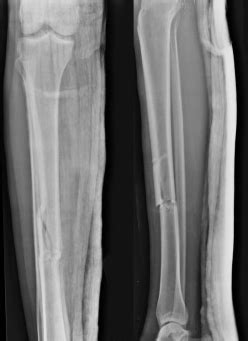

Tibia (Shinbone) Shaft Fractures - OrthoInfo - AAOS